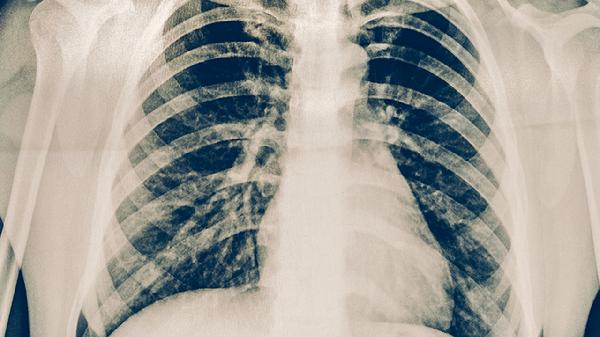

肺結(jié)核患者可選用百部、白及、黃芩三味中藥輔助治療,具有抑菌殺蟲、收斂止血、清熱燥濕的功效。